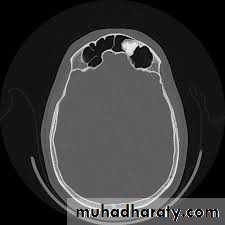

CT scan & MRI: show the tumor, bone erosion& extension of the tumor.

T4: Tumor invades orbital contents beyond the floor or medial wall including apex and/or any of the following: cribriform plate, nasopharynx, sphenoid sinus, frontal sinus.

T4: tumor with intracranial extension, orbital extension including apex, involving sphenoid and/or frontal sinus and/or nasal skin.